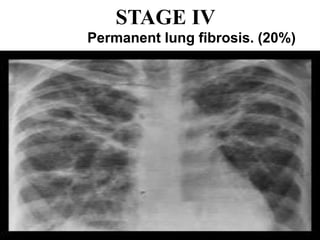

STAGE IV

Extensive pulmonary fibrosis is typically worst in

the upper lobes.

Broad bands of fibrosis in the upper lobes

Permanent lung fibrosis. (20%)